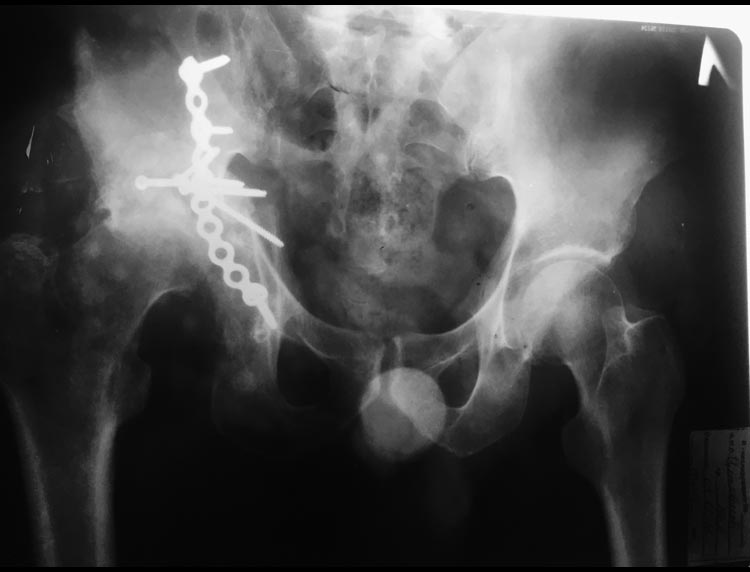

Уважаемые коллеги, помогите определиться с дальнейшей тактикой лечения

Из анамнеза: травму пациент получил в результате ДТП 12 месяцев назад.

Сочетанная травма ЗЧМТ. Сотрясение головного мозга. Трансвертлужный

перелом. Центральный вывих бедренной кости (первоначальные снимки

предоставить не могу).  2 месяца лечился методом скелетного вытяжения.

Через 4 месяца после травмы поступил в наше отделение. Пациенту

выполнена операция :  реконструкция вертлужной впадины с костной

аутопластикой с гребня подвздошной кости (дефект заднего края с полным

лизисом костных  отломков). Фиксация пластиной Матта. На сегодняшний

день (через 7 месяцев после реконструкции впадины) отмечается лизис

головки бедренной кости и укорочение абсолютной длины правой нижней

конечности на 5 см. Есть сомнения на счёт сращения аутокости. Как быть в

данной ситуации ? Спасибо